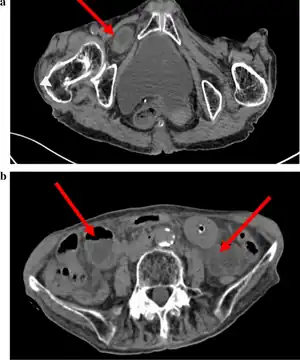

| Abdominal CT scan showing obturator hernia[1] | |

The diagnosis is often made during laparoscopic pelvic exploration after the person arrives at the hospital with signs and symptoms consistent with bowel obstruction. Laparoscopic pelvic exploration is a minimally invasive procedure that allows the surgeon to visually examine the contents of the abdomen without making a large cut.[5] The Howship–Romberg sign is suggestive of an obturator hernia, with about 56.2% (out of 146 patients in a systematic review) of people showing these signs.[2] These signs are worsened by thigh extension, medial rotation and abduction.[6] It is described as a sharp, stabbing pain in the medial thigh/obturator distribution, extending to the knee and is caused by the hernia pushing on the obturator nerve. The Hannington-Kiff sign can also be suggestive of an obturator hernia, which tests the adductor muscle reflex with a hammer whilst applying pressure on the obturator nerve.[7] However, due to its rare form, obturator hernias are difficult to diagnose due to many other possibilities, non-specific symptoms of pain, as well as minimal external signs/symptoms that can be seen without imaging. The current gold-standard for diagnosis of an obturator hernia is through abdominal computed tomography scans (CT scans), which has been used for diagnosis of 84.2% of patients in a recent systematic review for obturator hernias.[2]